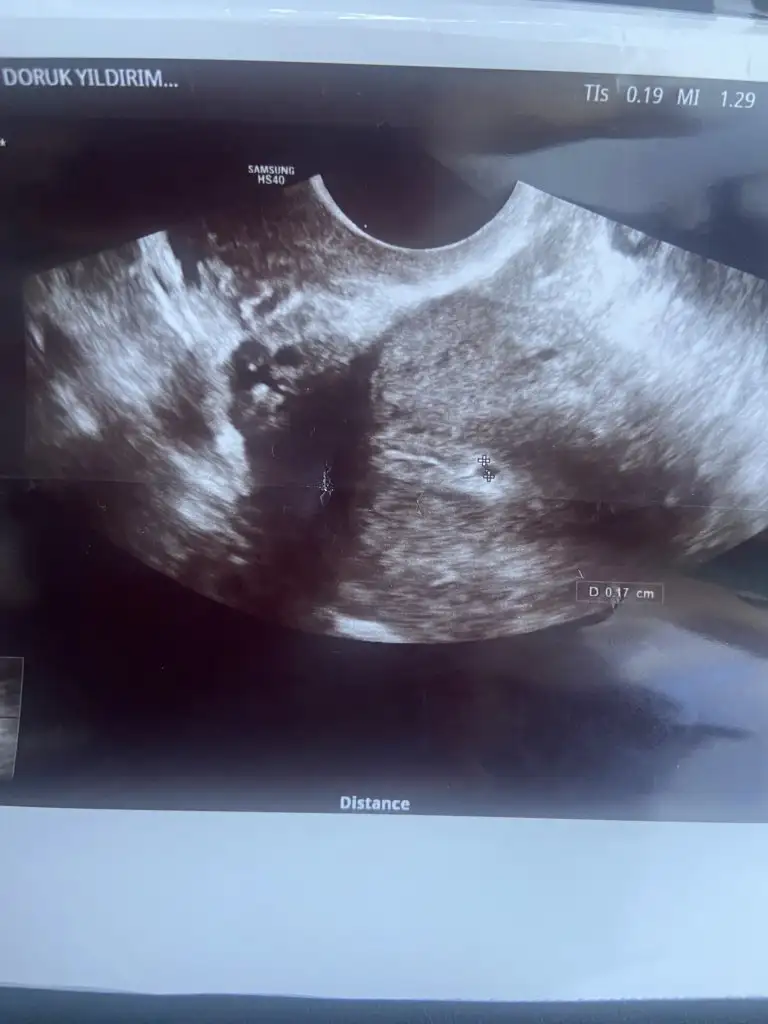

yükselişe bakıcak sanırım betanın birde rahiç içinde keseye benzer birşey gördü değer çok küçük ama bende gördüm bildiğiniz kese idi bende anlam veremedim hatta atayım fotoğrafını buraya bakın